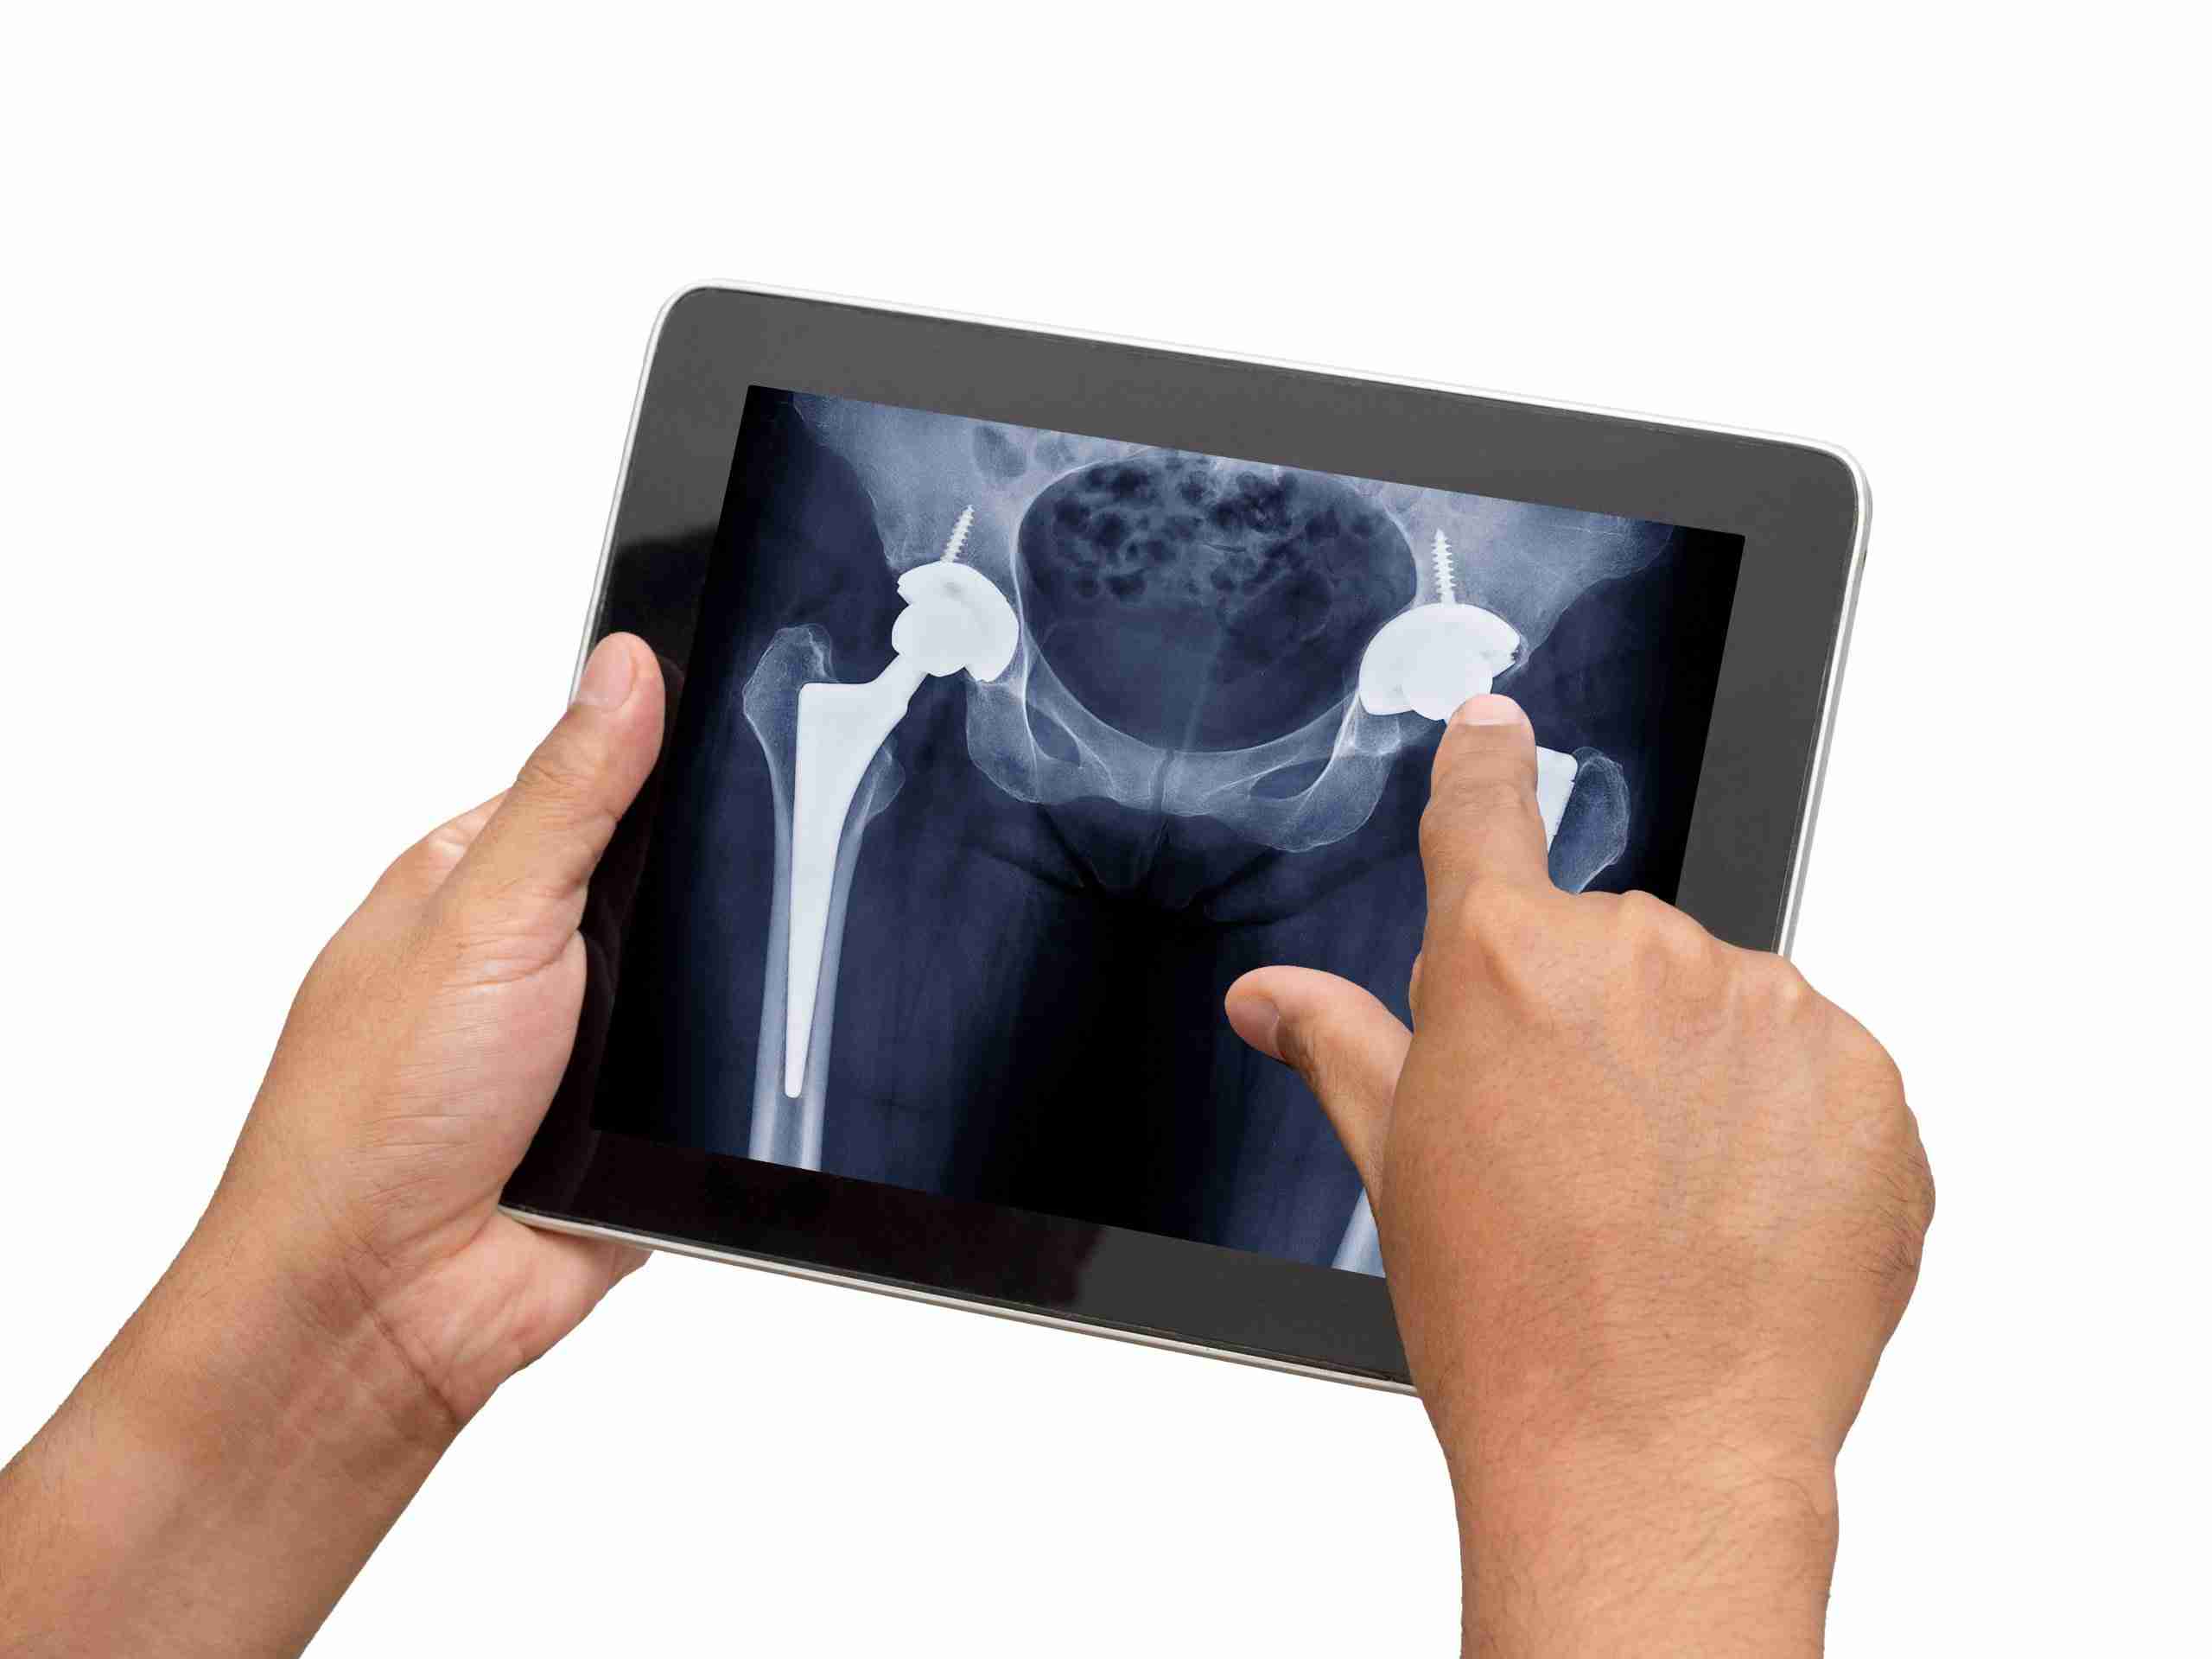

Hip replacements provide the ability to reduce severe pain and stiffness while improving function in over 400,000 people in the United States each year. There are different approaches your surgeon may take when replacing the hip joint. Read further to learn some tips and tricks to follow to ensure you have a speedy and healthy recovery.

There are a few differences in the beginning stages of recovery depending on the approach. Depending on your body shape, size, and status of your hip, your surgeon may approach the hip from posterior (the back side) or anterior (the front side).